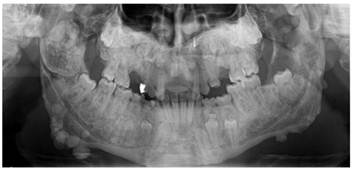

Figure 2

Panoramic view of the patient presenting multiple osteomas. A particularly large lobulated osteoma is present in the right condyle and coronoid process that impacted both permanent and deciduous teeth.

A 21-year-old patient was referred to the Department of Oral Surgery at Istanbul University, Istanbul, Turkey, for the management of craniofacial manifestations of GS. Intra-oral, extra-oral, and radiological examinations were performed. The patient came to our attention due to a primarily esthetic complaint about the right angle of the mandible. An initial clinical examination showed a nodular formation that was palpable along the mesial portion of the right mandibular angle (Figure 1). The oral mucosa was normal, and the regional lymph nodules were not palpable. A panoramic radiograph and an anteroposterior radiography showed the presence of multiple round radiopaque lesions in both the maxilla and mandible, multiple impacted teeth (upper right first, second premolar, upper right third molar, upper left canine, upper left first and second premolar, upper third molar, lower left canine, first and second premolar, and lower right canine, first and second premolar), and multiple odontomas, each measuring approximately 0.5 to 2 cm in diameter (Figure 2). On palpation, these lesions were hard, well limited, and non-adherent to the skin. Diffuse sclerosis could also be noted throughout the mandibular body. Neither crepitating nor clicking on mouth opening was noticed in the temporomandibular region bilaterally. Maximum mouth opening was not restricted (42 mm). No deviation of the mandible was observed, and no pain on mouth opening was evident. No trigeminal paresthesia was diagnosed, and the facial nerve function was preserved.

Osteomas are predominantly detected by routine panoramic radiography.15 Pain is rarely observed, and the disease is predominantly asymptomatic, but the lesions can cause facial asymmetry as a result of expansion.13 In addition to clinical palpation, dental panoramic radiography is an effective means of detecting multiple osteomas of the jaws that are characteristic of GS. Radiologically, the lesions are radio-opaque. In our patient, radio-opacities on the angle of the mandible were observed, and several impacted teeth in all segments of the jaws were evident. Increased difficulty of tooth extraction was present due to the high density of the alveolar bone, the limited mouth opening, and the loss of the periodontal space.16 Our diagnosis was performed by CT radiographs to detect osteomas and dental anomalies.